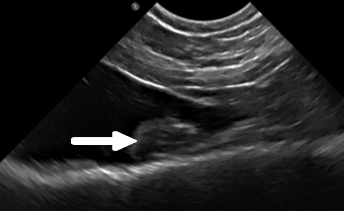

An advanced, highly practical ultrasound course designed to extend diagnostic capability, combining hands-on training in challenging abdominal structures, Doppler techniques and ultrasound-guided sampling for confident clinical application.

This course is suitable for you if you‘re a general practitioner who already has experience performing an abdominal ultrasound and would like to elevate your skills in evaluating the more challenging abdominal structures and at performing ultrasound-guided sampling. You’ll also learn how to use ultrasound for the assessment of the thorax (except heart) and neck, increasing the range of applications of this imaging modality that you can offer your patients. This two day Advanced Small Animal Ultrasound course will consist of a combination of lectures and several hands on practical sessions with the guidance of the course tutors.

- Become more proficient at identifying adrenal glands and pancreas, familiarising yourself with the different anatomical landmarks used to find these small organs and being able to differentiate normal appearance from pathological changes

- Gain improved confidence on evaluating difficult areas like the pylorus and urinary bladder trigone

- Identification of the major abdominal lymph nodes using the adequate anatomical landmarks and being able to differentiate normal appearance from pathological changes affecting these structures

- Introduction to Doppler techniques and the identification of portosystemic shunts with ultrasound

- Decide which ultrasound-guided tissue sampling technique is indicated for your patient, and become confident at performing ultrasound-guided fine needle aspirates

- Become familiar with the normal appearance of lung and being able to identify thoracic wall, pleural, pulmonary and mediastinal disease using ultrasound

- Identification of thyroids, parathyroids and cranial neck lymph nodes and recognise the typical ultrasound appearance of common diseases that can affect these structures.